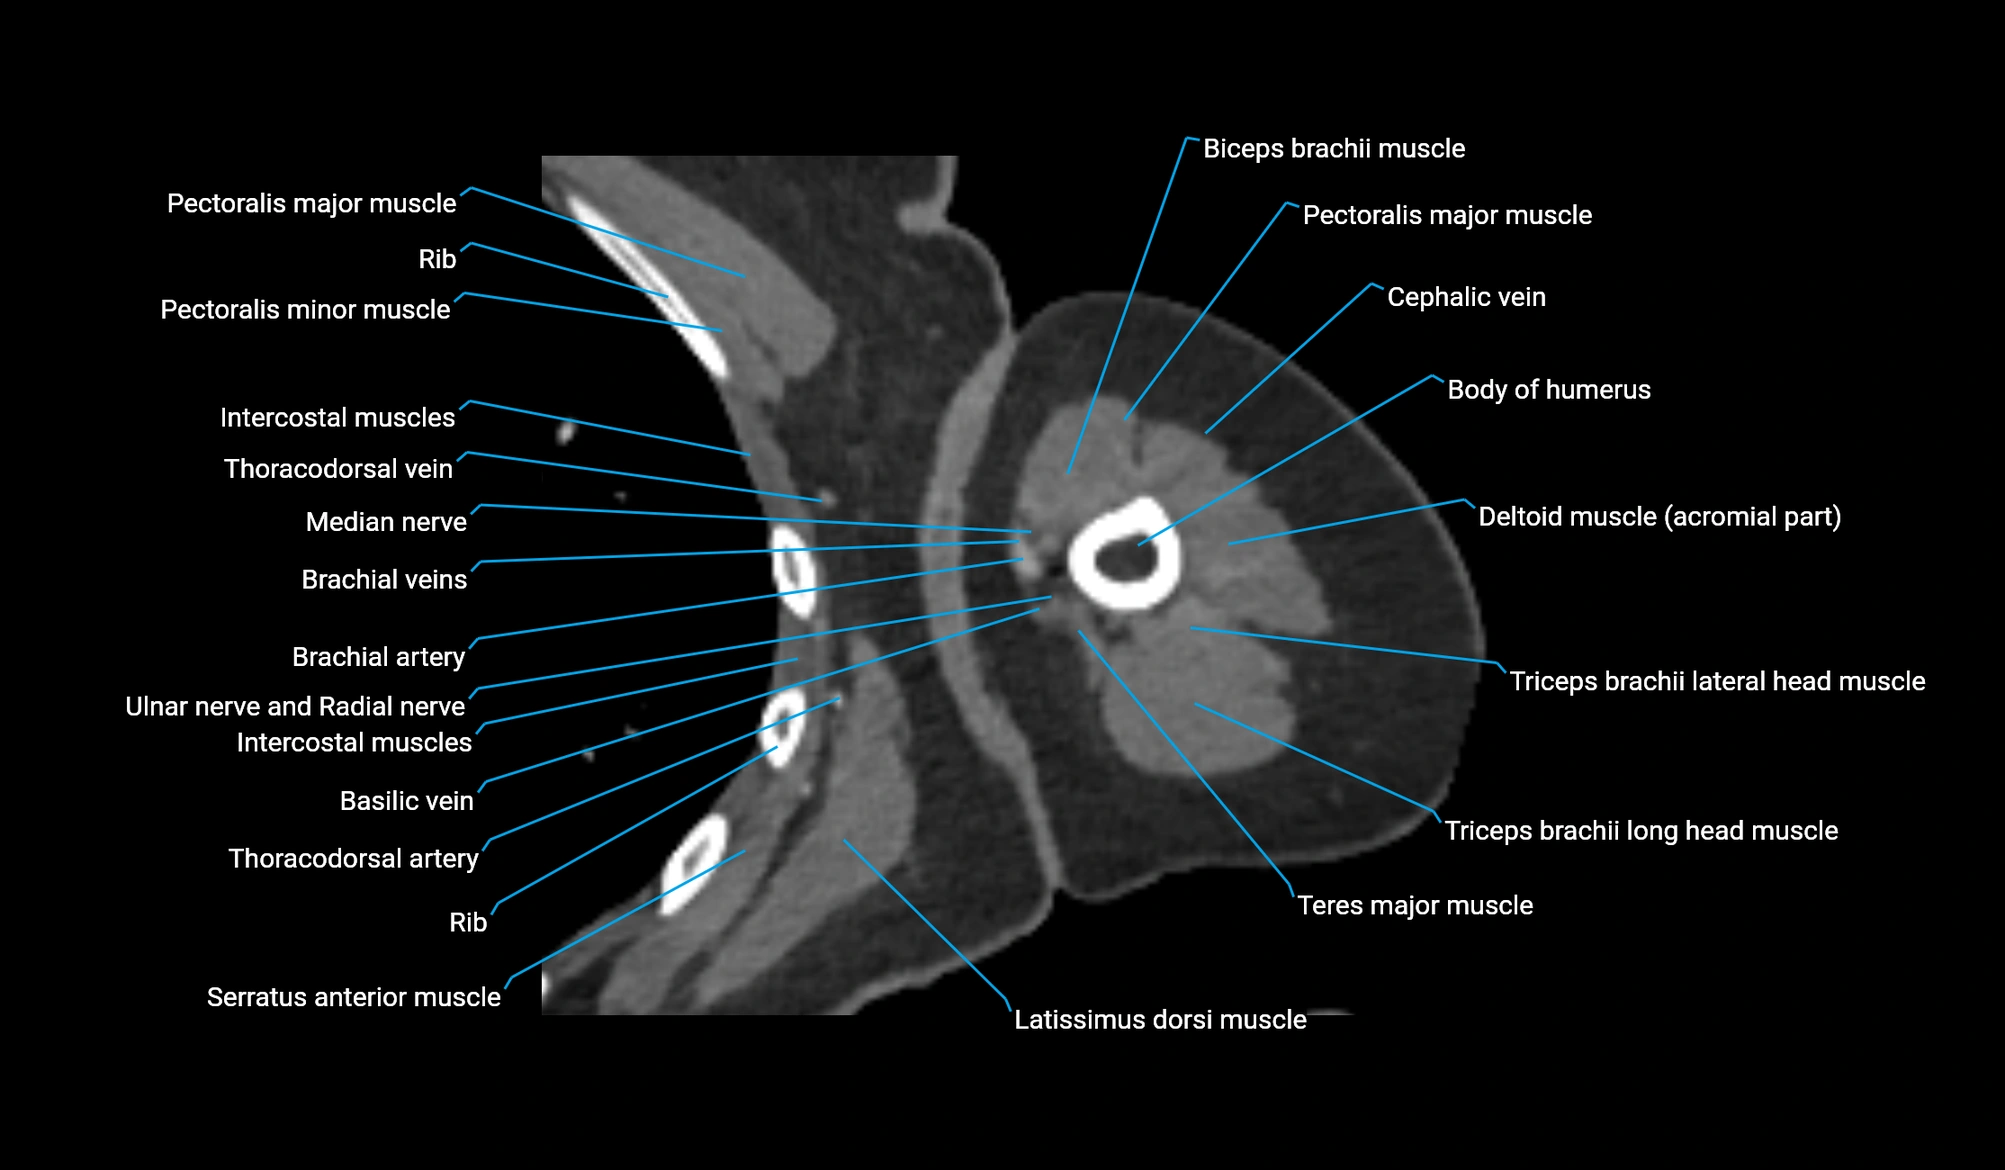

- Body of humerus

- Brachial artery

- Cephalic vein

- Deep brachial artery

- Median nerve

- Pectoralis major muscle

- Pectoralis minor muscle

- Radial nerve

- Superior ulnar collateral artery

- Teres major muscle

- Thoracodorsal artery

- Triceps brachii muscle